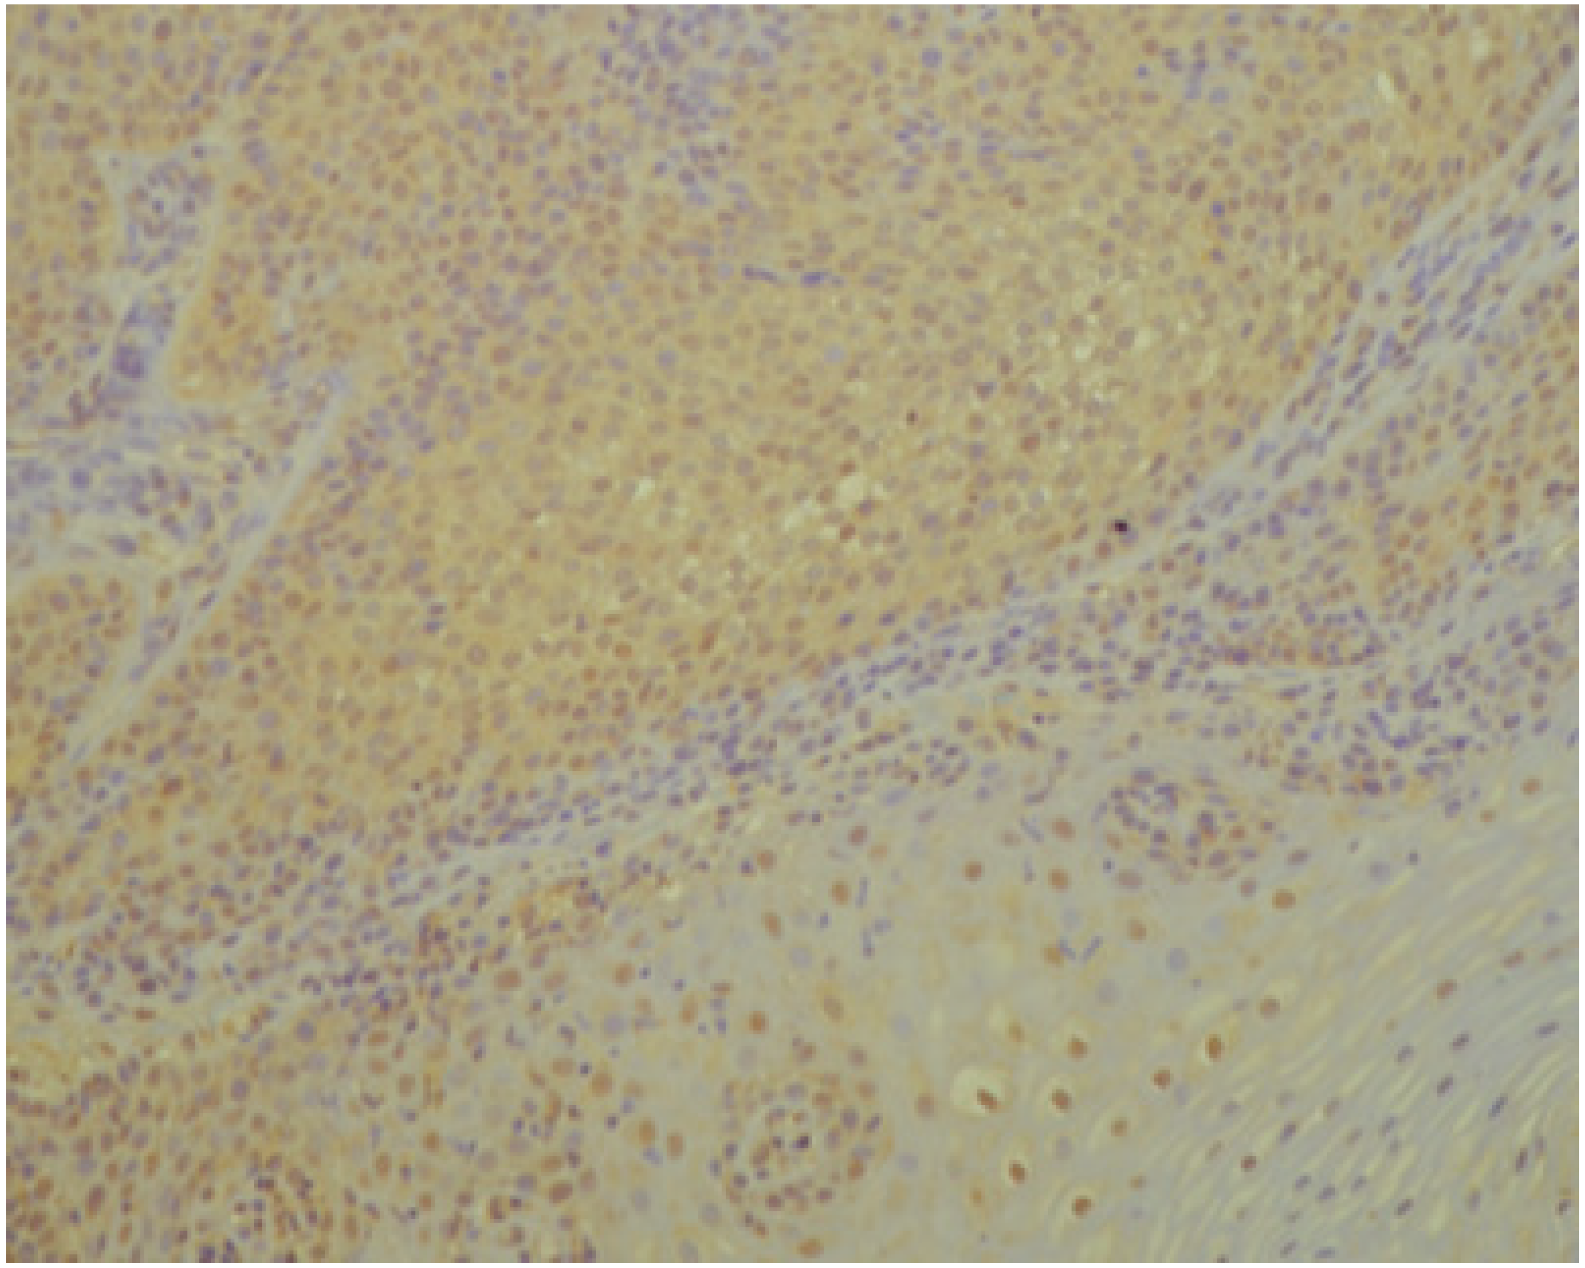

3.1. Histopathology and Immunohistochemistry